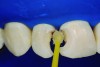

For the stepwise excavation, isolation with a rubber dam was performed prior to the removal of the infected tissue in the whole extension of the surrounding walls, with the aid of Nos. 3 and 4 rounded stainless steel burs at low speed. The disorganized dentin of the axial walls was removed with manual excavators (Figure 4). A 1-mm layer of calcium hydroxide paste was applied on the axial walls, and a GIC provisional restoration was performed; GIC was inserted with a syringe to avoid the incorporation of air bubbles into the material, thus, enabling better sealing. The option for a GIC relied on its good sealing properties, allowing more favorable conditions for the pulp-repairing activity.

Fig 4. Manual excavator removing tooth decay.

Figure 4